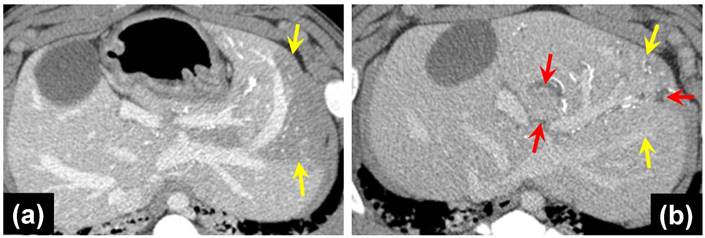

In the phase two study, all animals administered with control or VERB100 bead suspension received greater than 92% of the full dose prepared for administration (dose volume ranging from 18.5 to 20 mL). By fluoroscopic estimation, approximately 50 % of the liver volume was embolized in all animals. There was also no definitive difference in the distribution of the beads in the embolized liver. The appearance did not change from the Day 0 to the Day 30 or Day 90 repeat CT examinations (Figure 4).

No biliary ductal dilatation was noted on the Day 0 CTs of unloaded or drug loaded beads with targeted lobe sizes similar between both. Biliary dilatation was seen on 4/4 Day 30 CTs of the VERB100 group and 0/3 the Day 30 CTs of the ROB control group. The Day 90 CTs of the VERB100 group show 2/3 with biliary dilatation. The Day 90 CTs of the unloaded control group show 2/3 with biliary dilatation. Lobe size of both control group and VERB100 group were compared to initial appearance and adjacent non-targeted lobes. There was a reduced size of the targeted lobe in 6/7 VERB100 group (Figure 5(b)). The control group demonstrated decreased size in 0/6. This was noted to be present on Day 30 and Day 90 CTs. Areas of decreased perfusion on initial CT demonstrate decreased size on follow up CT. Again, the finding can be attributed to more effective embolization which would decrease lobule and hence lobe size.

Figure 3

30 Day coronal thin MIP reformations from CT acquisition showing the distribution of beads in one representative animal per group. There is no difference in CT visualization or density between VERBs of different drug doses.

Figure 4

MDCT axial images of the liver of VERB100 treated animals at (a) 1 hour post-embolization and (b) 90 Days post-embolization, showing no discernible differences in bead visibility.

Figure 5

(a) MDCT axial image of portal venous phase post contrast, 1 hour post-embolization with VERB100, yellow arrows point to areas of decreased hepatic parenchymal enhancement; (b) MDCT axial image of portal venous phase post contrast, red arrows indicate dilated bile ducts, yellow arrows show the reduced left liver lobe size 30 days post-embolization.